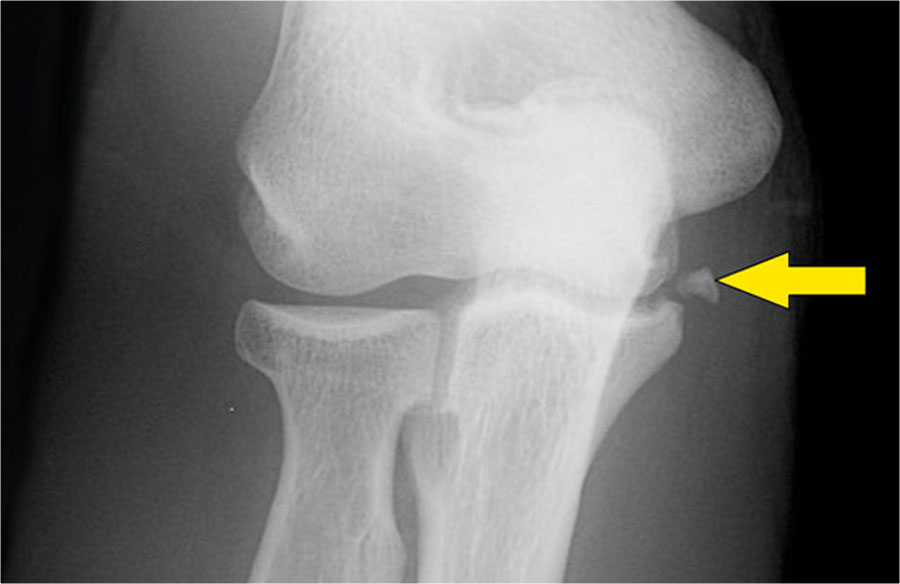

Đây là hình ảnh chụp X-quang tư thế nghiêng của khuỷu tay một bệnh nhân bị ngã chống tay duỗi thẳng.

Hình ảnh X-quang cho thấy tràn dịch khớp (mũi tên đỏ) và gãy mỏm vẹt (mũi tên vàng).

Continue with the MR-images.

Đây là hình ảnh MRI.

Hãy xem các hình ảnh và sau đó tiếp tục đọc…

Coronal view:

- Dây chằng bên ngoài bị bóc tách hoàn toàn (mũi tên vàng).

- radial head is subluxed.

- phù tủy xương của mỏm vẹt do gãy xương (mũi tên đỏ).

Sagittal view:

- Chỏm xương quay bị bán trật nhẹ ra phía sau (mũi tên vàng).

- Large effusion and capsular disruption posteriorly.

- Đụng dập mặt sau của chỏm con do va chạm với mỏm vẹt (mũi tên đỏ).

All these signs are the result of a posterior dislocation.